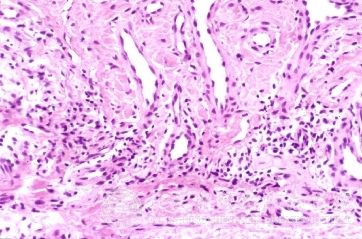

遗传变态反应性皮炎又称特应性皮炎或异位性皮炎,与遗传过敏体质有关,其特点是皮肤瘙痒,皮疹多形性并有渗出倾向,在不同年龄阶段有不同临床表现。患者常伴有哮喘、过敏性鼻炎及血清IgE增高等。